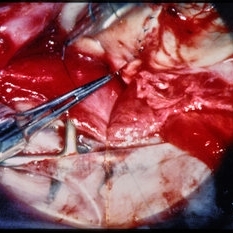

Surgical view repairing scleral rupture.

Condition/keywords: trauma